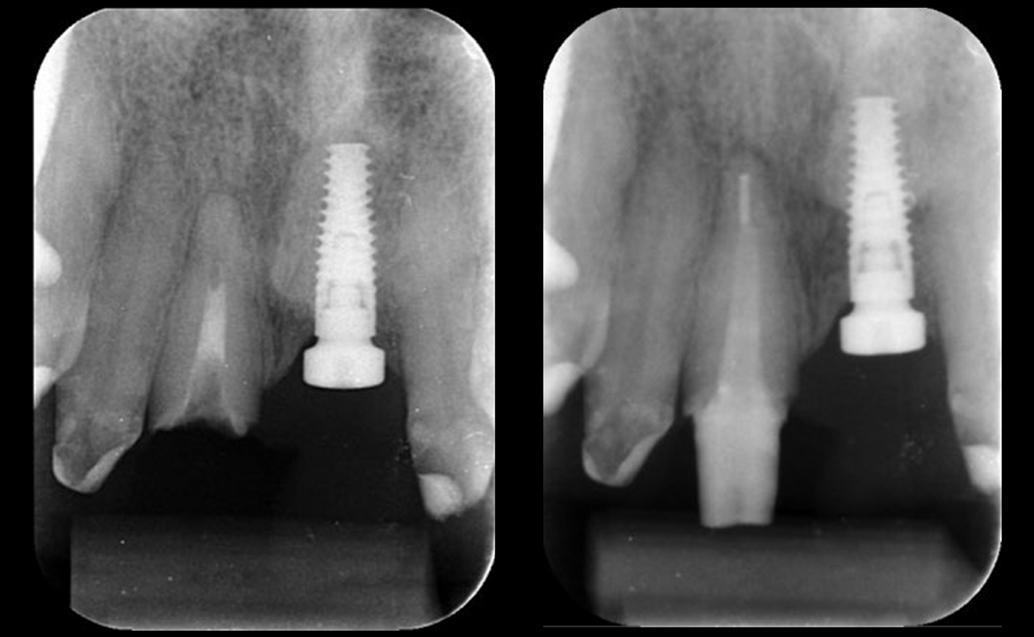

10. ábra. A négyéves kontroll alkalmával készült röntgenfelvételek. (A): A metszőfogakról készült koronafelvétel. (B): A jobb oldali szemfog és első kisőrlőfogról készült koronafelvétel. (C): A bal oldali szemfog és első kisőrlőfogról készült koronafelvétel.